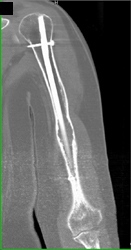

Tibial Fracture